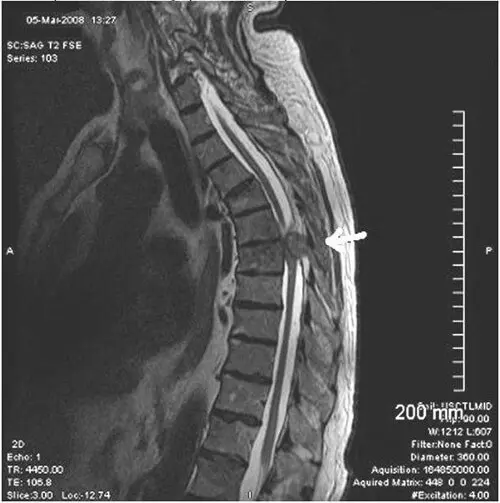

Пухлини грудного рівня

Можливі пухлини в грудному відділі хребта (див. МРТ нижче).

При болях в грудному відділі хребта обов’язково рекомендують МРТ для виключення пухлин і метастазів (знімок МРТ нижче).